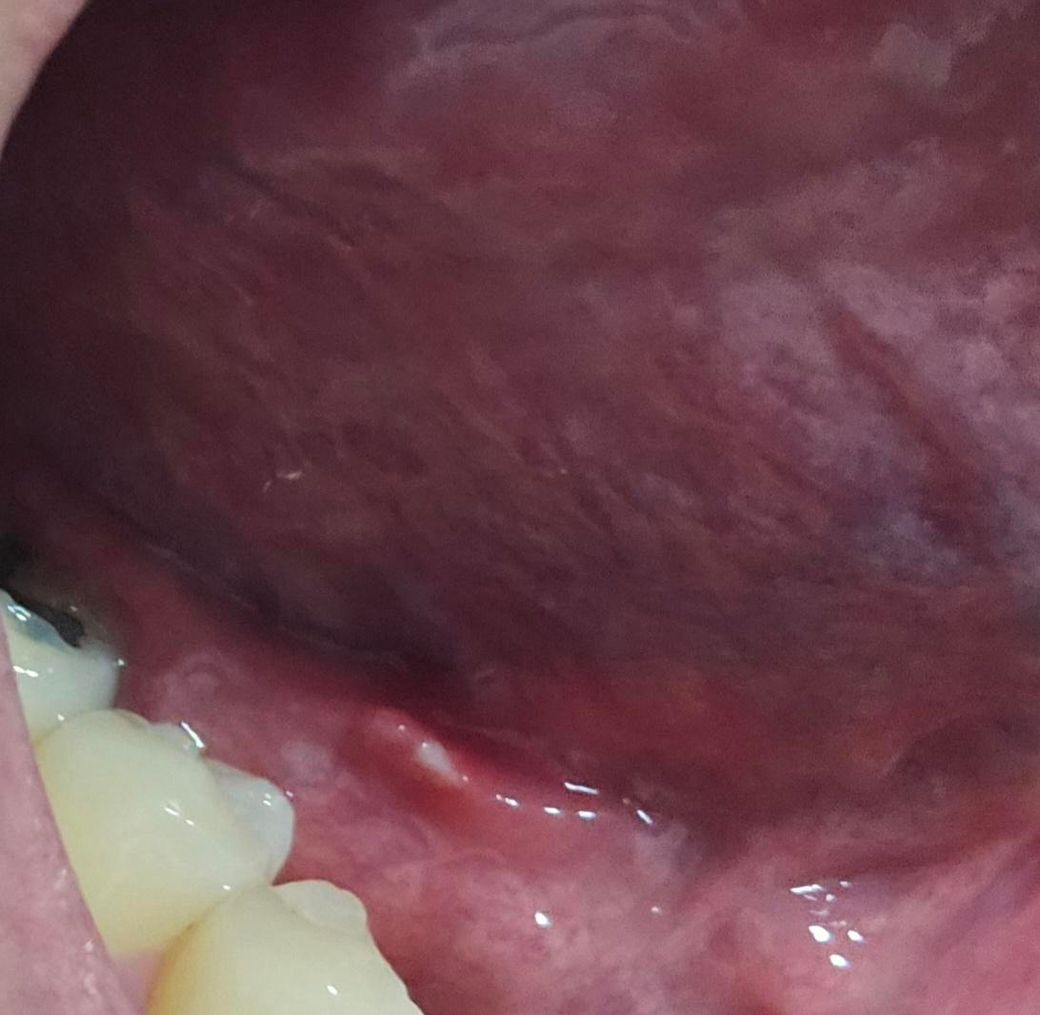

사진 첨부합니다. 혀 밑에 염증이 생겼는데 염증이 생기는 원인과 지금 생긴 염증의 이름이 있다면 알려주세요. 자연치료에는 얼마나 걸릴지도 여쭤봅니다

사진으로는 정확한 진단 불가능하며 병원 방문하셔서 직접 육안으로 진료 보셔야 합니다특히 올려주신 사진은 너무 어두워서 병변이 잘 안보여요. 확인 불가입니다

우선 말로 말씀하신 부분 관련 답변 드리자면 혀 밑에 생긴 염증은 보통 설하염(혀 밑 염증) 또는 구강 점막염의 일종일 가능성이 있습니다. 원인은 다양할 수 있는데, 대표적으로는 구강 위생 불량, 바이러스(특히 헤르페스), 세균 감염, 기계적 자극(예: 이물질, 잘못된 칫솔질), 영양결핍(특히 비타민 B군 부족), 스트레스 등이 있습니다.

때로는 치아나 틀니 문제, 혹은 알레르기 반응으로도 염증이 생길 수 있구요. 만약 염증 부위가 붓거나, 고름이 차거나, 통증이 심하면 세균성 감염이 진행된 것일 수도 있어요

자연치료는 염증의 원인과 심한 정도에 따라 다르지만, 가벼운 경우라면 보통 1주일 내외로 저절로 호전됩니다. 이 기간 동안은 구강을 청결히 하고, 자극적인 음식(매운 것, 뜨거운 것, 딱딱한 것)을 피하는 것이 중요합니다. 염증이 2주 이상 지속되거나 통증이 심해지면 반드시 병원을 방문하여 진료를 받아야 합니다